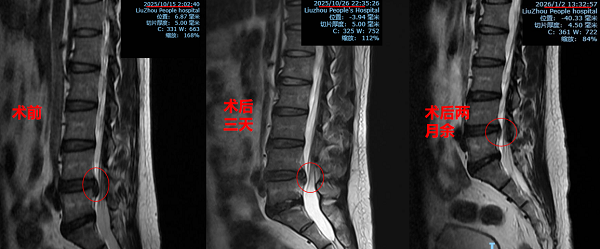

術后三天,石先生的疼痛評分從6分降至1-2分,麻木感減輕;兩個月后隨訪,他已恢復正常工作生活,術后評價達到“優”級標準,椎間盤突出物縮小40%。